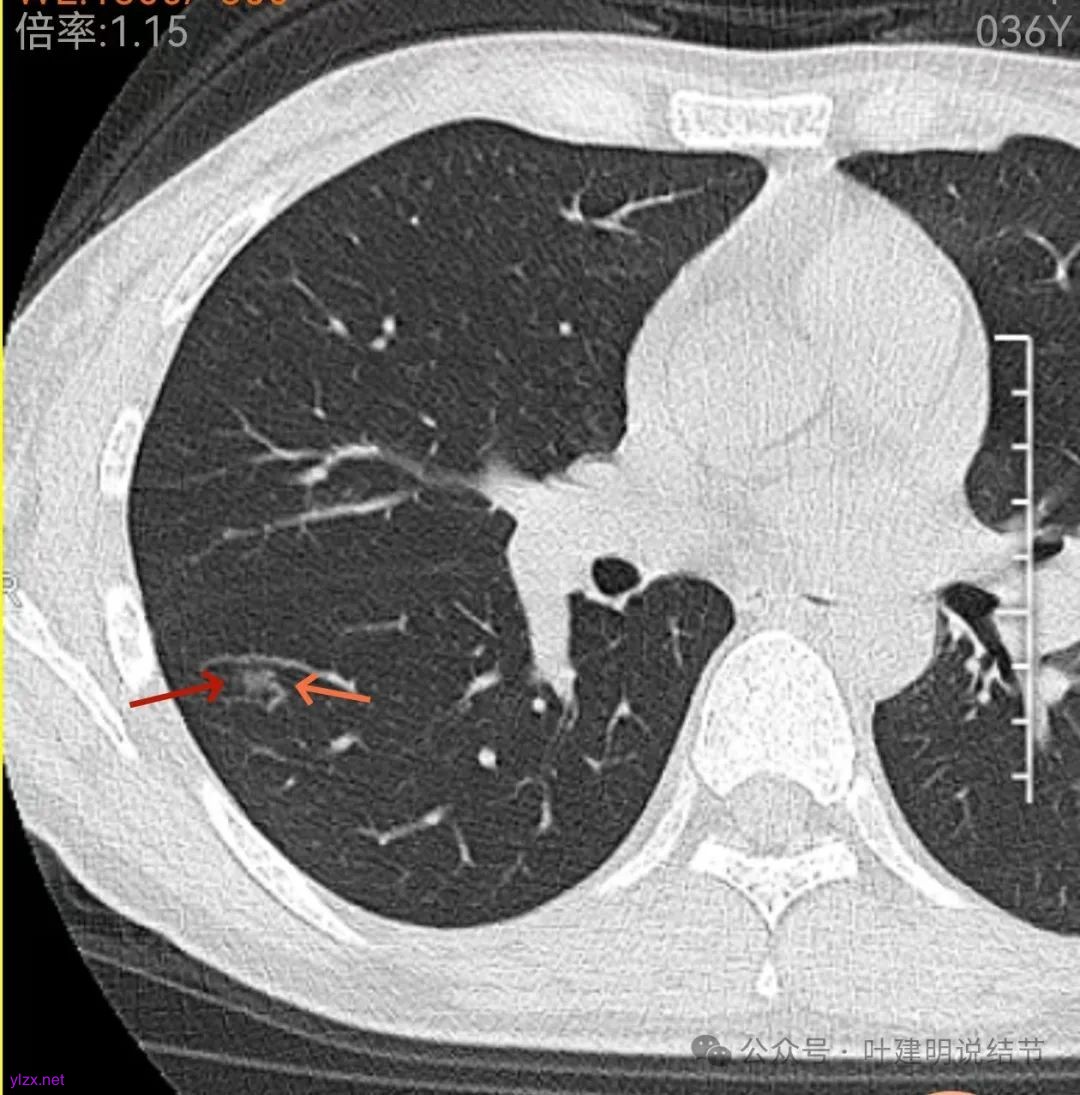

上图层面已经像混合密度了,表面毛糙不光滑,灶内密度不均,也有小空泡征的样子。

感觉这处(在上截图结节的下面点,邻近层面)不像前面病灶的延伸,否则这密度的变化有点突兀呀。

两肺多发结节,左侧黄色标注的考虑是肺泡上皮增生可能性大;蓝色的考虑肺泡上皮增生或者少许慢性炎可能性大;右侧红色宽起来并带有红色箭头的这处是主病灶,偏混合密度,整体轮廓较为清楚,边缘显得毛糙,从2024年12月份的来看,要考虑是肿瘤范畴,原位癌或者微浸润性腺癌可能性较大,也不能完全排除不典型增生。但是在2022年的时候,这个病灶的边上也有一个实性的微小结节,如果只看2022年的,这么小的实性结节,又比较圆,表面也显得较为光滑,是要考虑良性的,当然太小了需要动态观察。回头再重新来看2024年底的,发现绿色箭头所指的这个微小实性的较2022年几乎没有变,去仔细寻找2022年的,发现当时在实性结节旁边也有密度很淡的一点磨玻璃影(也可能真的就是一处,只是扫描不够薄,密度的变化有些突兀而已),而到了2024年12月份,实性微小这处没有明显变化,但是原来很淡的磨玻璃变成了混合磨玻璃,范围也明显扩大。所以总体来看右肺下叶这处是考虑恶性的,而且从磨玻璃结节角度来讲,还是生长比较快的,就是说还是有一定风险的。加上左侧还有两处也是磨玻璃持续存在,虽然边缘轮廓显模糊一点,但多年以后也可能仍然要变成原位癌或者微浸润性腺癌之类的东西。通盘考虑以后,我倾向于右侧近期单孔胸腔镜下微创局部切除,左侧随访观察,等到有进展并风险增加再来考虑处理。意见供参考!

这位结友目前仍未反馈给我结果,但偏混合密度的这处显然是像肿瘤范畴的。现在有些不太确定的是,到底是不是边上有颗偏实性的结节一直在,而且进展不明显,而原来很淡的这处磨玻璃结节却在2年内明显进展了?抑或本身就是同一处?但若是同一处,就是2022年和2023年的反而是点状高密度,2024年的却整体病灶各层面的密度都不如前面的高,这用肿瘤解释不通呀。当然,右下这个病灶前后对比来看,恶性的概率是大得多,随访进展还是切了为好。期待后续能有反馈。